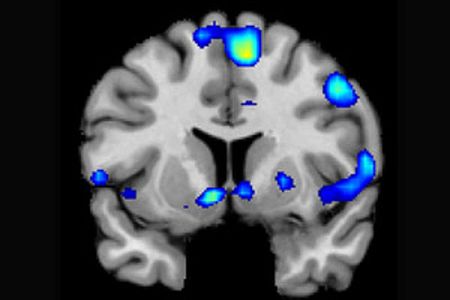

Diversas áreas del cerebro, activas durante la experiencia religiosa de los participantes.

Diversas áreas del cerebro, activas durante la experiencia religiosa de los participantes. SINC

Basándose en las imágenes del IRMf , los científicos descubrieron que los sentimientos espirituales intensos se asocian con la activación del núcleo accumbens, un grupo de neuronas del encéfalo a las que se atribuye una función importante en el placer y el sistema de recompensa.

Aparte de las redes neuronales ligadas al sistema de recompensa, también se descubrió que los sentimientos espirituales se asocian a la corteza prefrontal media (una zona cerebral que se activa por acciones relacionadas con valoraciones, juicios y razonamiento moral) y otras regiones del cerebro asociadas a la atención focalizada.